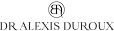

L’endodontie est la spécialité dentaire qui concerne le traitement de la pulpe dentaire, c’est-à-dire la partie interne de la dent où se trouvent les nerfs et les vaisseaux sanguins. Lorsqu’une carie profonde, un traumatisme ou une infection atteint cette zone, un traitement endodontique devient nécessaire pour préserver la dent et éviter son extraction.

Au cabinet du Dr Duroux à Cannes, ces soins sont réalisés avec précision grâce à des techniques modernes et des équipements adaptés, permettant de nettoyer, désinfecter et obturer les canaux radiculaires de façon durable.